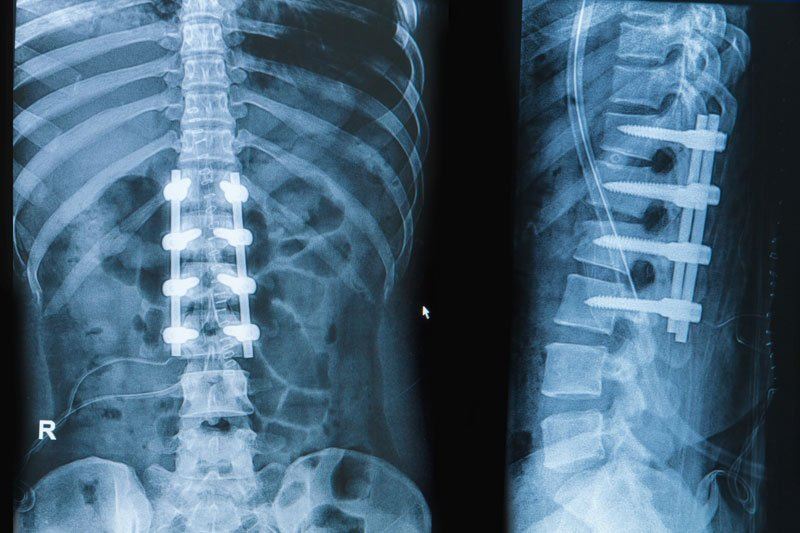

- X-rays – to show changes in disc height, bone spurs, or spinal alignment.

Surgical Treatments

- Spinal Fusion: A surgical procedure that fuses two or more vertebrae to provide stability and reduce motion at the affected segment of the spine.